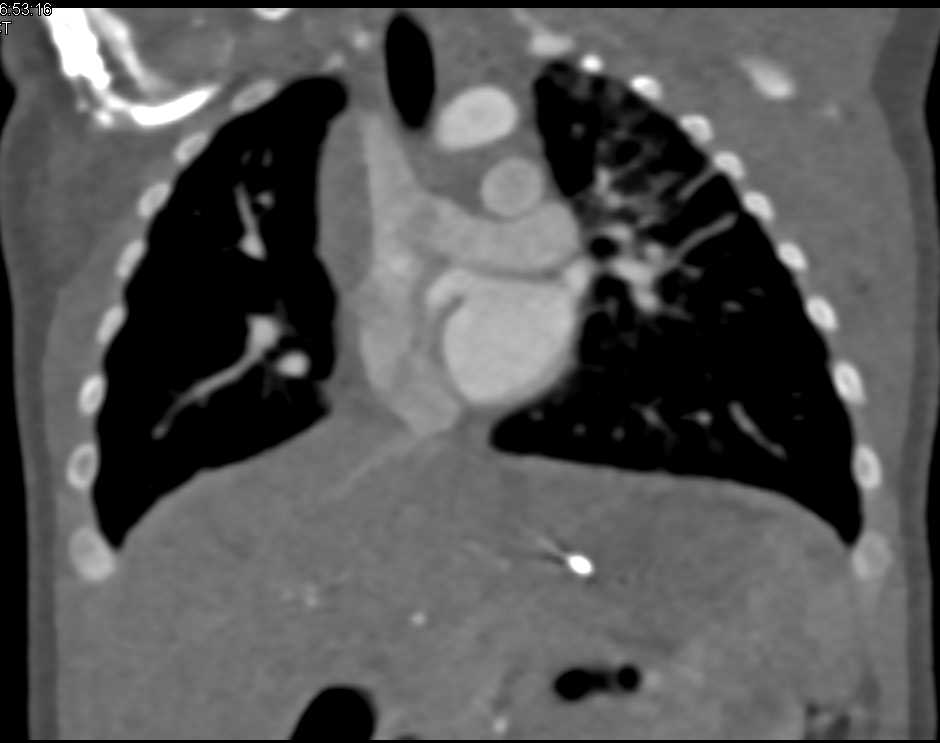

3D Vascular Mapping for Pediatric Vascular Display and Lung Display